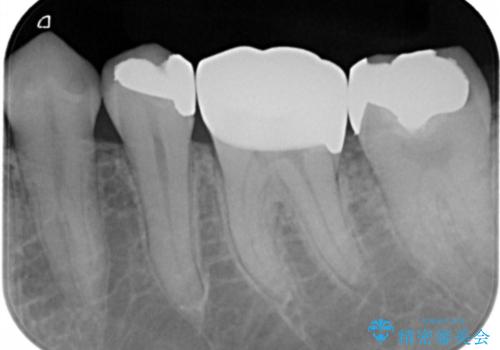

切削量などを考慮し、フルジルコニアクラウンでの治療を選択しました。

う蝕が深く切削量が多くなりましたが痛みなどは起きなかったので、予定通りフルジルコニアクラウンでの治療で進めました。